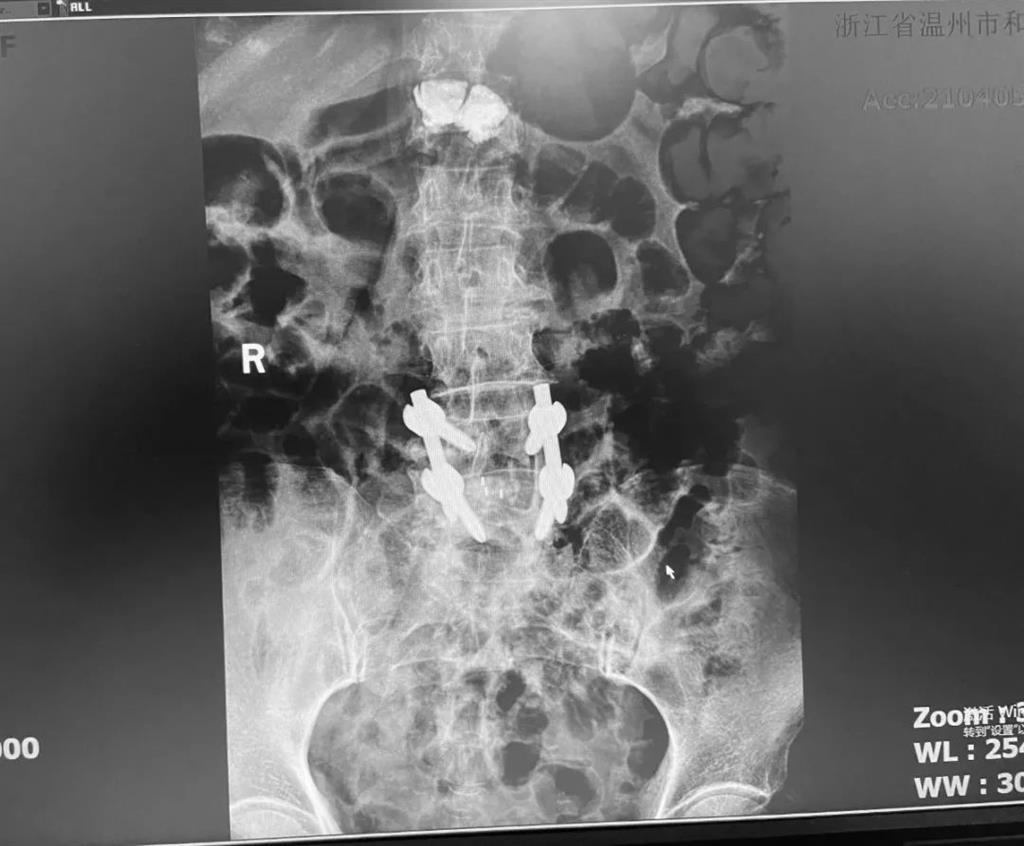

據(jù)了解,脊柱內(nèi)鏡下腰椎融合術(shù)只需要打幾個“鑰匙孔”即可完成。聽起來是不是很簡單?在脊柱內(nèi)鏡下,劉丹主任先后為患者進(jìn)行了椎管減壓、椎間盤摘除,再實(shí)施椎弓根螺釘放置、椎體植骨融合內(nèi)固定,一系列步驟有條不紊。

看似簡單的幾個步驟,但實(shí)際上很復(fù)雜,需要主刀醫(yī)生有豐富的手術(shù)經(jīng)驗(yàn)和細(xì)致耐心的操作。

術(shù)中只需切開4個如“鑰匙孔”般大小的孔道